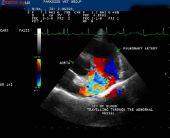

Специализация: патология и клиника на домашни любимци. Вътрешни болести и кардиология. Клинична дейност и научни интереси, свързани с диагностика и лечение на кардиомиопатии при кучета и котки, с фокус към митрална болест при кучета и хипертрофна кардиомиопатия при котки.

Вродени сърдечни заболявания при кучета и котки